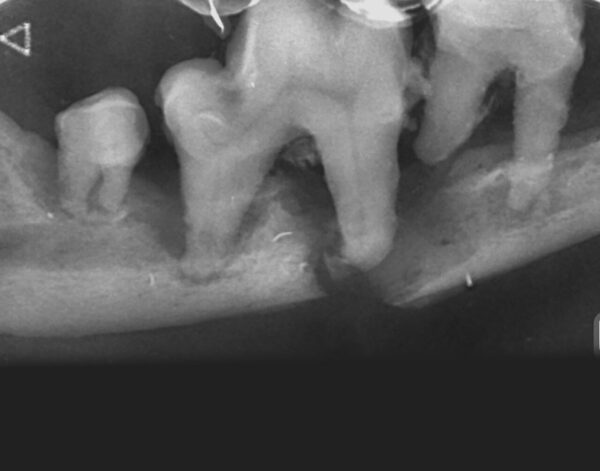

- Grado 2 (PD2): pérdida del soporte óseo menor al 25 % (imagen 7).

- Grado 3 (PD3): pérdida del soporte óseo de un 25-50 % (imagen 8).

- Grado 4 (PD4): pérdida del soporte óseo mayor de un 50 % (imagen 9).

Además de permitirnos evaluar el grado de enfermedad periodontal, también hace posible seleccionar el mejor tratamiento en función de su patología y las posibles complicaciones, como las fracturas mandibulares iatrogénicas en perros de talla pequeña con enfermedad periodontal PD4 (imágenes 10 y 11).